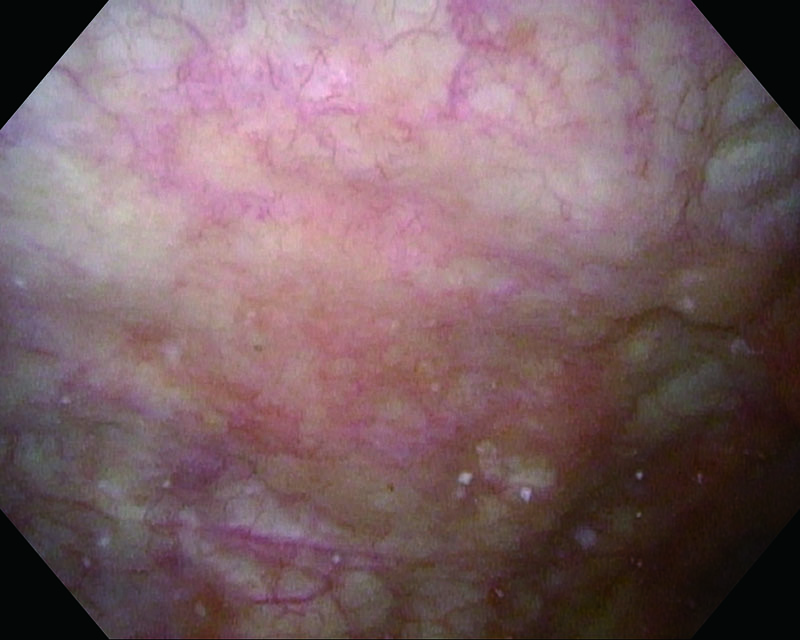

Rubor mucosa, age 81, male

White Light

NBI™ Technology

Histology UC, CIS

Comments

The case suspected carcinoma in situ and identified rubor bladder mucosa. Histopathologic examination revealed CIS.